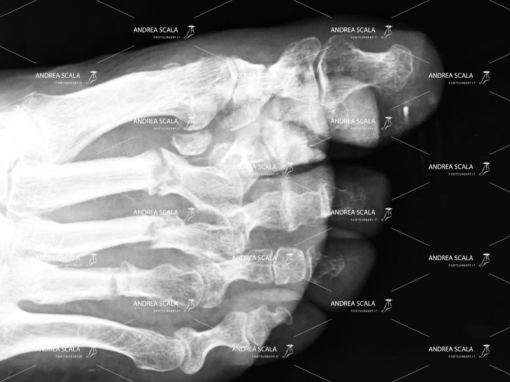

Con il termine “alluce valgo” ci si riferisce a una patologia che non colpisce propriamente solo l’alluce, ma tutta la parte anteriore del piede. Molto semplicemente, si tratta di una deviazione dell’alluce verso l’interno, ovvero verso le altre dita, che causa un particolare rigonfiamento laterale in corrispondenza della testa del primo metatarso.

Questa tencnica prevede l’uso di un frullino che viene messo sotto la pelle della paziente (percutanea). Il chirurgo quarda la Rxgrafia, ma non osserva con gli occhi ciò che sta facendo sotto la pelle (percutanea). Il frullino ad alta velocità taglia l’osso e alcune volte anche tendini, vasi e nervi. Al termine dell’intervento l’osso tagliato viene lasciato libero di guarire senza alcun sostegno e senza alcuna guida. Osserviamo in ambulatorio casi molto gravi in cui l’osso è guarito storto o non si è più riattaccato.

L’operazione dell’alluce eseguita con tecnica mininvasiva (con una minima incisione).

Il dott. Andrea Scala ha messo a punto una tecnica, pubblicata in U.S.A. nel 2013 che supera i problemi che la tecnica percutanea comporta.

Grazie a questa tecnica è possibile sezionare l’osso deformato per riposizionarlo e riallinearlo con le altre dita del piede, il tutto effettuando solo un’incisione di pochi millimetri sulla cute. La minima incisione taglia l’osso con precisione ed evita di tagliare anche tendini, vasi e nervi. Al termine dell’intervento un piccolo chiodo di 1 millimetro aiuta l’osso tagliato a guarire nella posizione corretta e assicura che l’alluce operato non tornerà mai più.